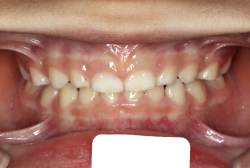

下顎前突・反対咬合

反対咬合とは、歯の生えてくる角度が悪くて下の前歯が上の前歯の外側に出てしまう”歯性反対咬合”と、上下の顎の骨の大きさと形に問題があることで起きる”骨格性反対咬合”に大別されます。骨格的な問題がないか、あったとしても軽度な場合は、大人でも矯正治療で改善することが出来ます。矯正治療のみで治せるのか外科矯正を併用した方が良いのかは、検査診断後に矯正専門医とよく相談して決めていただきます。

初診時の状態ですが、前歯の噛み合わせが逆転していて、下の前歯が外側に来て、上の前歯が裏側になっています。口元の様子ですが、前歯の重なり方が逆なので、唇の様子もそれを反映して、下唇が突出しています。反対咬合としてはかなり重症です。

分析してみると歯の傾き方に問題があるだけでなく、顎の骨の大きさと形にも問題があることが分かりました。ただし、骨の問題点が見つかったからと言って、必ずしも外科矯正になるわけではなく、このくらいの症状ですと、通常の矯正でもきれいに治すことができます。

診断の結果、下の前歯を正しい位置まで内側に入れていくためには、十分な隙間を確保することが避けられないと判断し、上の左右第二小臼歯と下の左右第一小臼歯は抜歯させて頂くことにしました。歯の本数は減りましたが、歯科医学的評価も大きく改善しましたし、審美的にも大幅な改善が見られますね。特に口元の様子が全然変わりました。